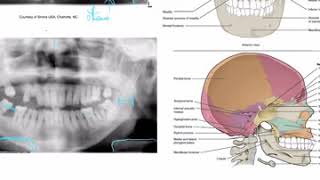

Anatomical Landmarks Found in a Panoramic Radiograph Content

Panoramic Radiographic Anatomy Information

Panoramic Radiography - Anatomical Landmarks